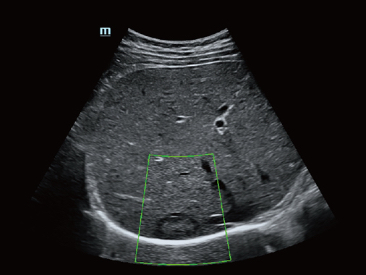

Desde que a empresa foi fundada, a Mindray est├Ī continuamente explorando novas maneiras de melhorar a confian?a no diagn├│stico. Alimentada pela mais revolucion├Īria tecnologia ZONE Sonography?, a nova plataforma Resona 7's ZST+ traz uma qualidade de imagem ultra-som a um n├Łvel superior por aquisi??o de zona e processamento de dados do canal.

Assim como o n├Łvel de qualidade de imagem premium, o Resona 7 tamb├®m melhora as capacidades de investiga??o cl├Łnica com o revolucion├Īrio Fluxo V para avalia??o hemodin?mica vascular e a aquisi??o de plano mais inteligente do conjunto de dados 3D para diagn├│stico CNS fetal. Combinando a opera??o mais intuitiva baseada em gesto de multi-toques e todos os recursos cl├Łnicos essenciais, Resona 7 est├Ī realmente conduzindo novas ondas na inova??o de ultra-som.